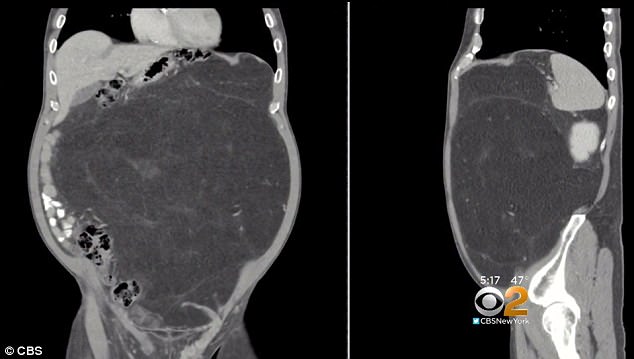

Kevin Daly, de 63 años, pensaba que estaba muy gordo, por lo tanto comenzó a realizar ejercicios y a comer de forma saludable.

El hombre logró bajar de peso, pero su panza seguía exactamente igual.

Eso alarmó muchísimo a este hombre de Hoboken, Nueva Jersey.

“Pero después de la pérdida de peso, no perder un gramo de mi estómago, no tenía lógica”, dijo Daly, y los doctores estuvieron de acuerdo, por lo tanto decidieron realisarle algunas pruebas.